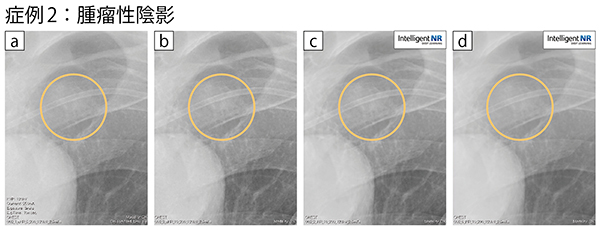

a:従来NR+通常処理 b:従来NR+処理検討後 c:INR+処理検討後 d:INR+通常処理

a,dの比較では,dの方がコントラストが良く見やすい。cはINRに適した画像処理であることから,一番陰影が見やすい。